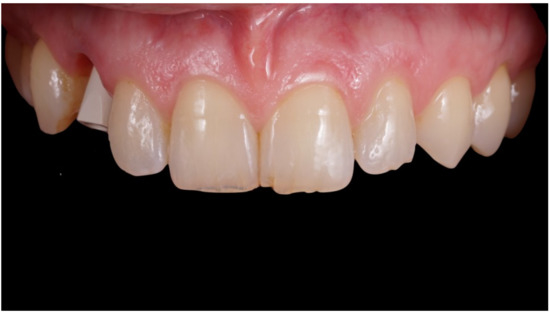

Figure 2.

Lateral preoperative view.